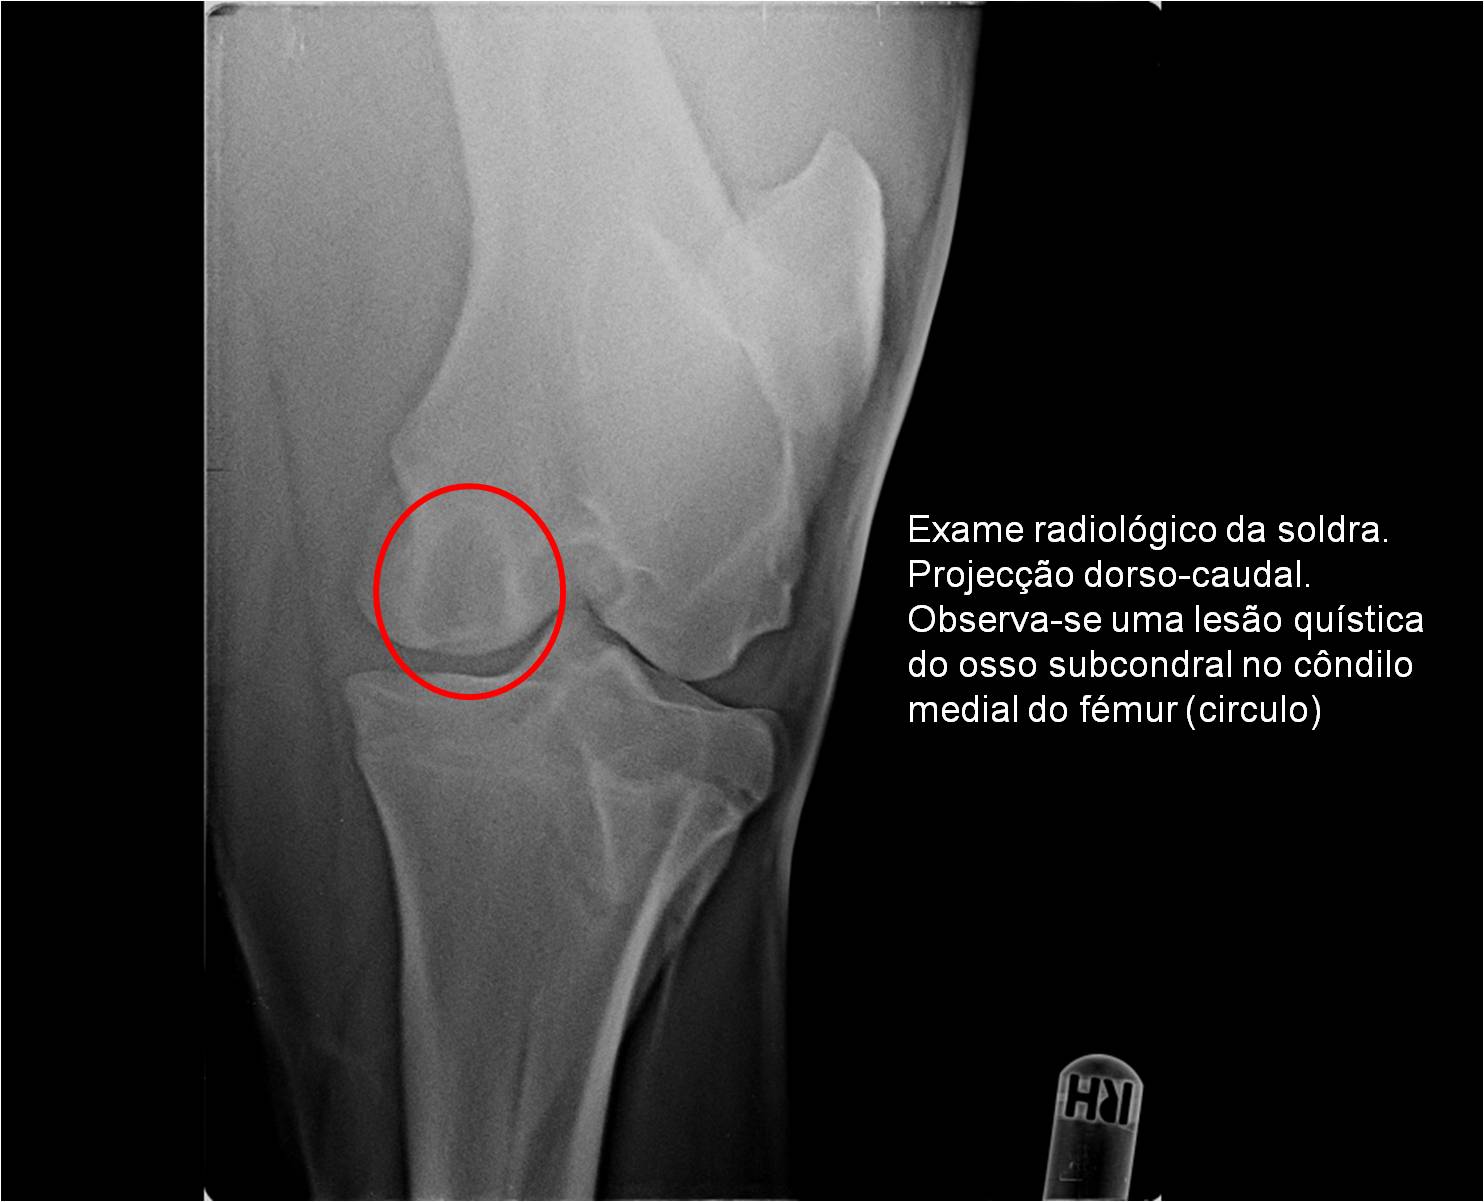

Publisher: Universidade de Évora

Abstract: O relatório de estágio encontra-se estruturado em três partes distintas. A primeira parte faz a caracterização das infraestruturas e funcionamento do Hospital Veterinário de Equinos de Lüsche, Oldenburg, Alemanha, assim como a análise casuística dos casos clínicos acompanhados durante os 6 meses de estágio. A segunda parte consiste de uma revisão bibliográfica sobre quistos do osso subcondral em equinos. Por fim, a terceira parte consta da apresentação e discussão de um caso clínico, nomeadamente o diagnóstico e acompanhamento imagiológico, por ressonância magnética, de um quisto subcondral na terceira falange num cavalo adulto; ### Abstract Equine Practice- Subcondral bone cyst of the third phalanx This internship report is divided in three parts. The first part characterizes the infrastructure and function of the Equine Hospital Lüsche, Oldenburg, Germany, as well as the casuistic of the clinical cases accompanied during the 6 month internship. The second part consists in a bibliographic review of cystic lesions of the subchondral bone in equines. The third part consists in a case report, the diagnostic and imagiological accompaniment, by use of magnetic resonance imaging, of a subchondral bone cyst in the distal phalanx of an adult equine.